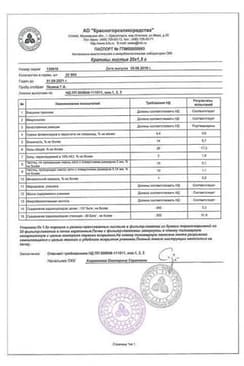

Крапивы листья ф/пак.1,5 г 20 шт

Сертификаты